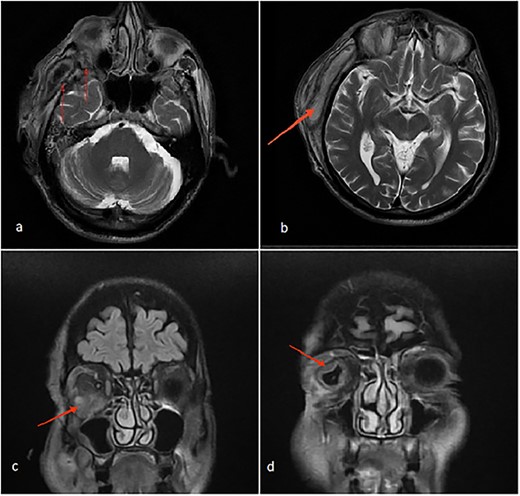

The patient’s head and neck were imaged using magnetic resonance imaging (MRI) and computed tomography scan, which revealed the presence of abscess collections in the submasseteric space, pterygomandibular space, deep temporal space and infratemporal abscess spreading to the orbital cavity through a bony defect in the lateral orbital wall, all of which were not addressed during the first procedure (Figs 2 and 3).

(a) Axial MRI of the head: a dumbbell-shaped lesion (red arrows) representing an infratemporal abscess invading the orbital cavity through the bony erosion of the lateral orbital wall. (b) Abscess localization in the deep temporal space (red arrows). (c, d) Coronal MRI of the head and neck shows an orbital abscess (red arrows) and endopthalmitis (red arrows).

Most cases of odontogenic orbital complications arise from upper jaw tooth infections [4]. What is unique about our case is the unusual route by which the infection spread into the orbit. In our case, the hypothesized path of spread started from the lower third molar infection to both the submasseteric and pterygomandibular spaces and then passed into the infratemporal fossa, where a focus of abscess was loculated, making its way into the orbit through a bony defect in the lateral orbital wall, forming an interesting dumbbell-shape appearance on MRI (Fig. 2a).